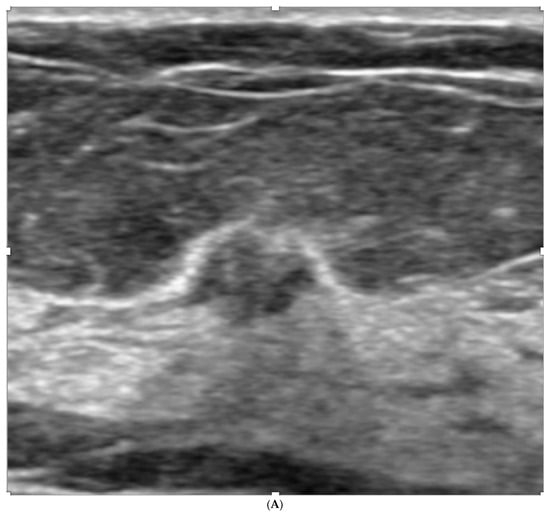

5. Ultrasound (US)